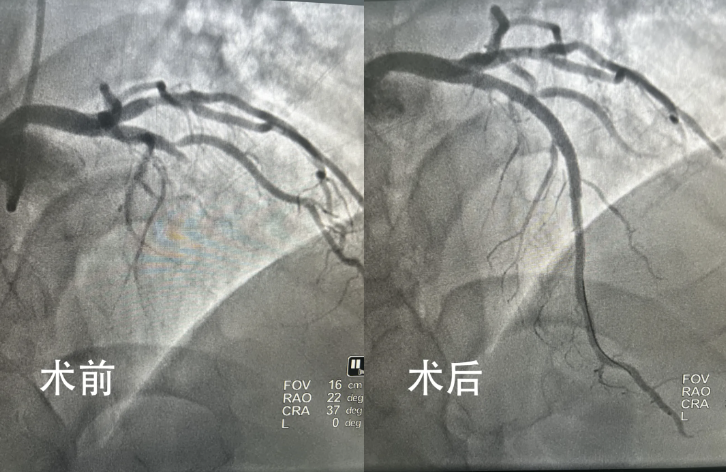

“消毒、铺巾、局麻、造影”一气呵成,造影结果显示,患者的前降支近端100%闭塞。此刻,整个团队心头的压力几乎化作了可以触碰的重量——每分每秒都关乎生死。没有一丝迟疑,导丝穿过血管的闭塞段、球囊预扩、支架植入,整个操作如行云流水,没有一丝停顿,每个动作都精准迅速,仿佛时间已不再是敌人,而是救命的希望。

随着患者的血管开通,血流恢复正常,患者的上腹痛症状立刻明显缓解。从急诊接收患者至手术顺利完成送入心内二科重症监护病房,仅仅用时不到30分钟。